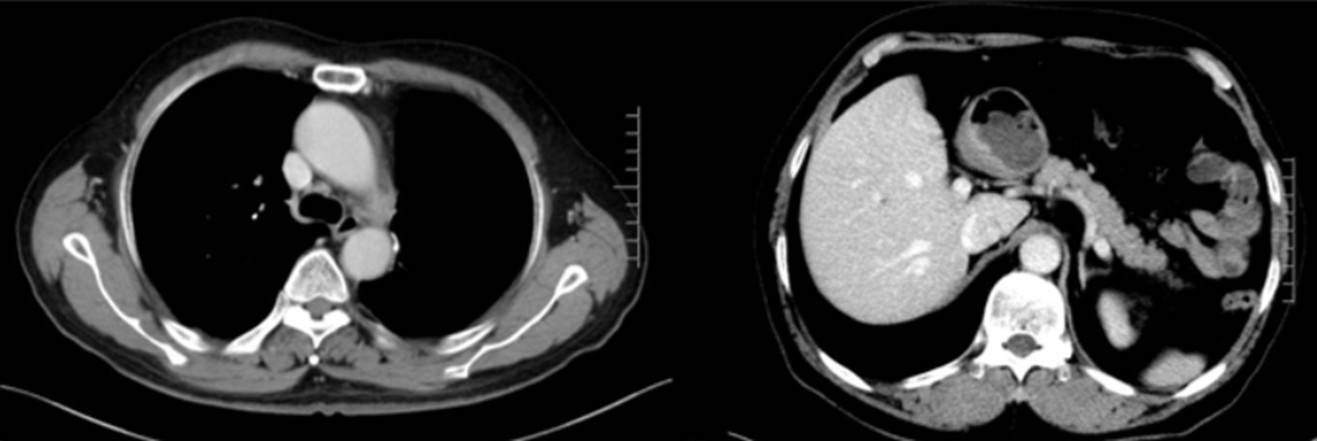

影像学检查:2023年10月16日CT示左侧锁骨上区、纵隔及左肺门区多发淋巴结部分较前稍增大(22mm),肝S4段结节(10mm),考虑转移瘤;脑MRI、骨扫描未见转移;

2023年12月4日(4周期后):左侧锁骨上区、纵隔及左肺门区多发淋巴结转移瘤较前缩小,肝S4转移瘤较前缩小;

2024年3月4日(5月后):左侧锁骨上区、纵隔及左肺门区多发小淋巴结大致同前,肝S4转移瘤显示不清;